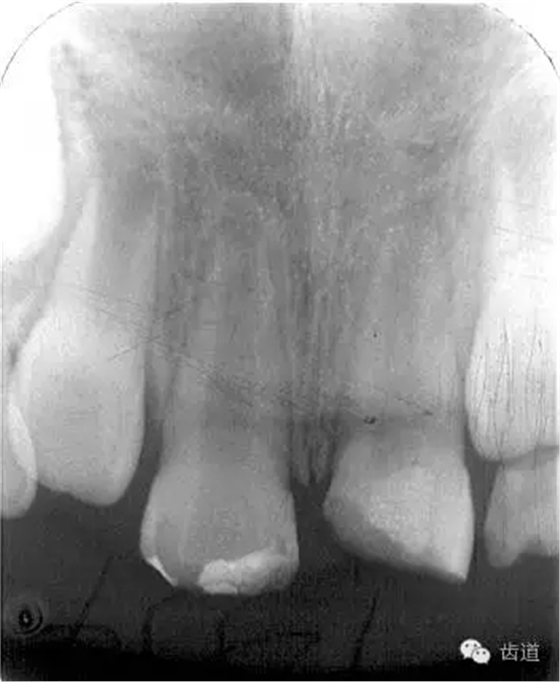

術(shù)后一個(gè)月

術(shù)后11個(gè)月